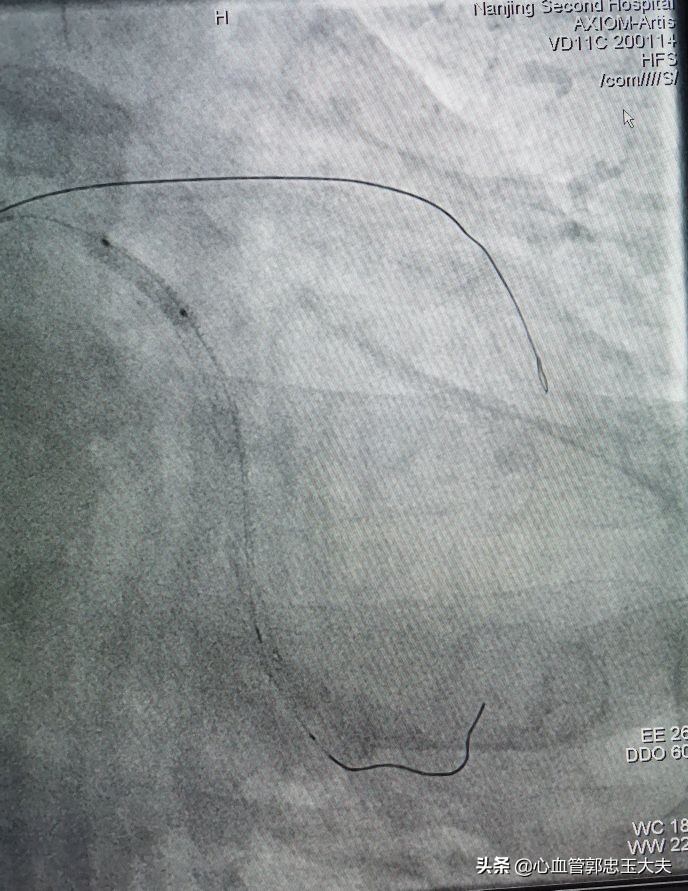

手术策略:计划先开通前降支中远段闭塞段,术*考前**虑到中远段完全闭塞合并钙化,因此开通难度特别大,也跟家属做了充分沟通。EBU大腔到位,回旋支BMW导丝到位加强支撑。FielderXT及Pilot50及150通过困难,反复尝试,FielderXT终于通过闭塞段。如下图

1.5*15mm微球囊通过病变血管困难,在回旋支预埋球囊,扩张加强支撑,微球囊仍然难以通过闭塞病变(如下图)